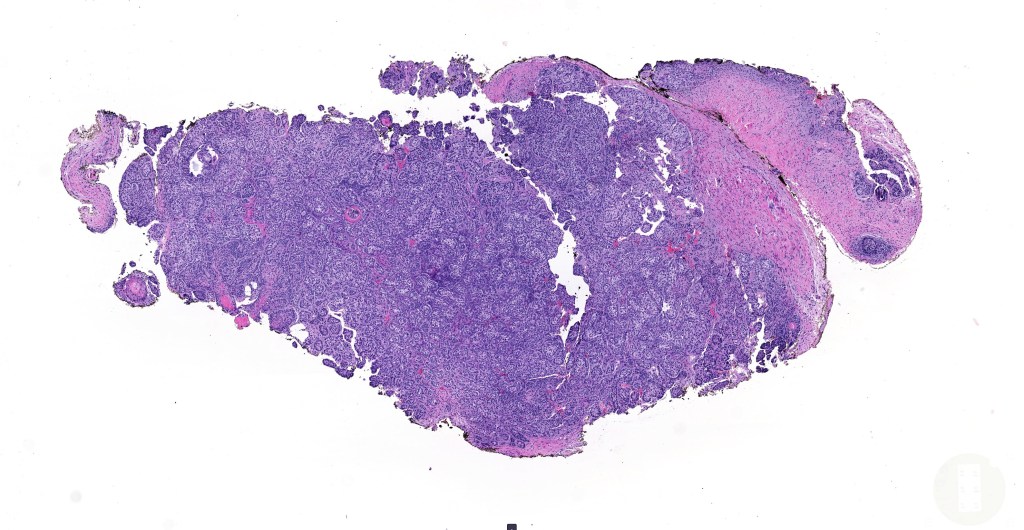

•Low grade trichoblastic carcinoma is easily recognized as trichoblastomatous but shows an infiltrating margin with deep involvement into subcutaneous fat +/- muscle

•High grade trichoblastic carcinoma is characterized by high grade carcinoma arising in a trichoblastoma. TP53 &PIK3CA mutations have been documented

•Trichoblastic sarcoma is characterized by readily recognizable trichoblastoma associated with a high grade sarcomatous element